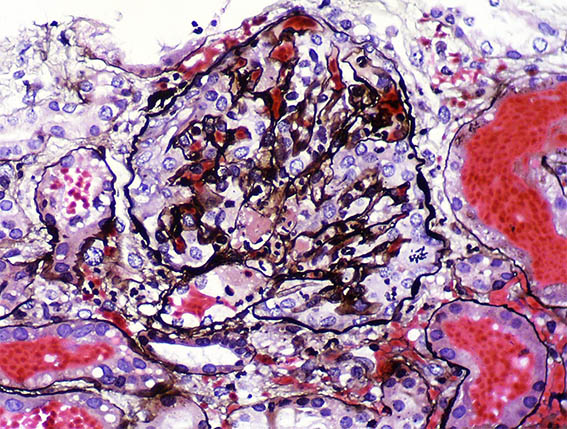

Figure 8. Methenamine-silver stain, X400.

Figure 9. Methenamine-silver stain,

X400.